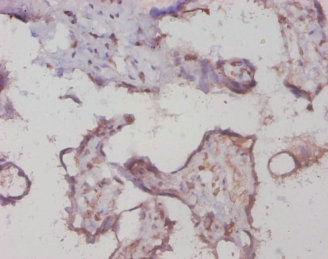

ApplicationELISA, WB, IHC; Recommended dilution: WB:1:1000-1:5000, IHC:1:20-1:200